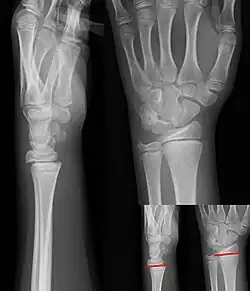

Salter–Harris fracture

A Salter–Harris fracture is a fracture that involves the epiphyseal plate (growth plate) of a bone, specifically the zone of provisional calcification.[2] It is thus a form of child bone fracture. It is a common injury found in children, occurring in 15% of childhood long bone fractures.[3] This type of fracture and its classification system is named for Robert B. Salter and William H. Harris who created and published this classification system in the Journal of Bone and Joint Surgery in 1963.[4]

There are nine types of Salter–Harris fractures; types I to V as described by Robert B. Salter and William H. Harris in 1963,[3] and the rarer types VI to IX which have been added subsequently:[5]

• Type I – transverse fracture through the growth plate (also referred to as the "physis"):[6] 6% incidence

• Type II – A fracture through the growth plate and the metaphysis, sparing the epiphysis:[7] 75% incidence, takes approximately 12-90 weeks or more in the spine to heal.[8]

• Type III – A fracture through growth plate and epiphysis, sparing the metaphysis:[9] 8% incidence

• Type IV – A fracture through all three elements of the bone, the growth plate, metaphysis, and epiphysis:[10] 10% incidence

• Type V – A compression fracture of the growth plate (resulting in a decrease in the perceived space between the epiphysis and metaphysis on x-ray):[11] 1% incidence